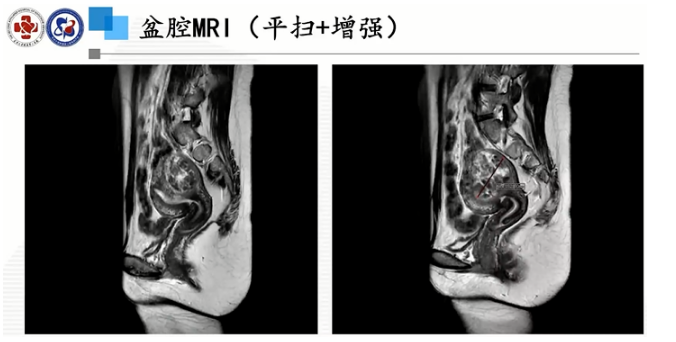

盆腔MRI(平扫+增强):

提示

1.子宫体后壁两处异常信号灶,考虑子宫肌瘤(较大一个考虑变性),其中一枚大小约45*42*55mm;

2.盆腔少量积液;

3.直肠后方小囊肿。